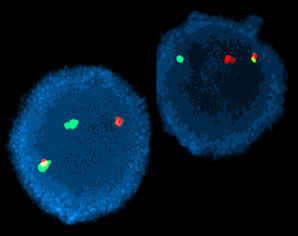

Cytogenetics: t(9;22) on conventional karyotype

FISH: Fusion of BCR and ABL1 probes

Moelcular: RT-PCR demonstration of BCR-ABL1 fusion

Rare cases may have cytogenetically cryptic BCR-ABL1 rearrangement

CML: FISH major breakpoint; Red=ABL, Green = BCR